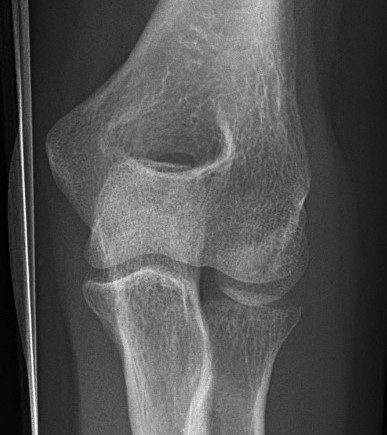

Hotchkiss modification of Mason Classification

Type 1: Undisplaced fracture / Intra-articular displacement < 2mm/ No mechanical limitation to forearm rotation

If in doubt, inject LA into radiocapitellar joint / soft spot and rotate elbow

Type I radial head fractures

Type 2: Displacement > 2mm / Motion mechanically limited / Reconstructable

Type 2 radial head fractures

Type 3: Severely comminuted fracture / Non reconstructable

Type 3 radial head fractures

Type 4: Radial head fracture with elbow dislocation

Type 4 radial head fractures